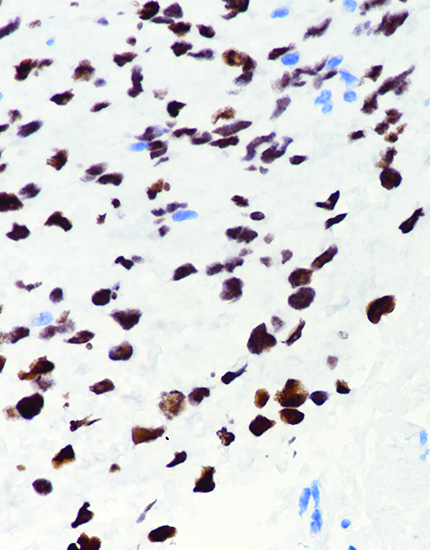

产品名称:H3 K36M

产品编号:RMA-0841

阳性部位:胞核

图片描述:

软骨母细胞瘤,H3 K36M染色,胞核阳性